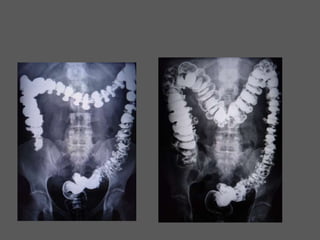

Divertículos

DIVERTICULITE